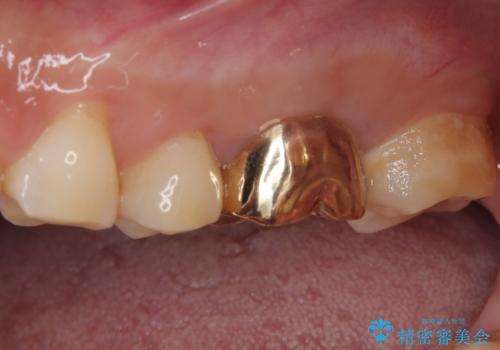

咬み合わせが非常に強く、臼歯のみに咬合力が集中している咬み合わせだったので、根管治療後はPGAクラウン(白金加金合金クラウン)にて補綴する治療計画となりました。

初回の根管治療を終えた2日後には膿の出口が消失し、咬んだときの不快な痛みもなくなりました。

PGAクラウンにしたことで咬み心地に全く違和感がなく、気にされていた審美面も、奥歯でありそれほど目立たないこともありますが、白金加金の色を気に入っていただけたので、患者様には大変満足していただけました。